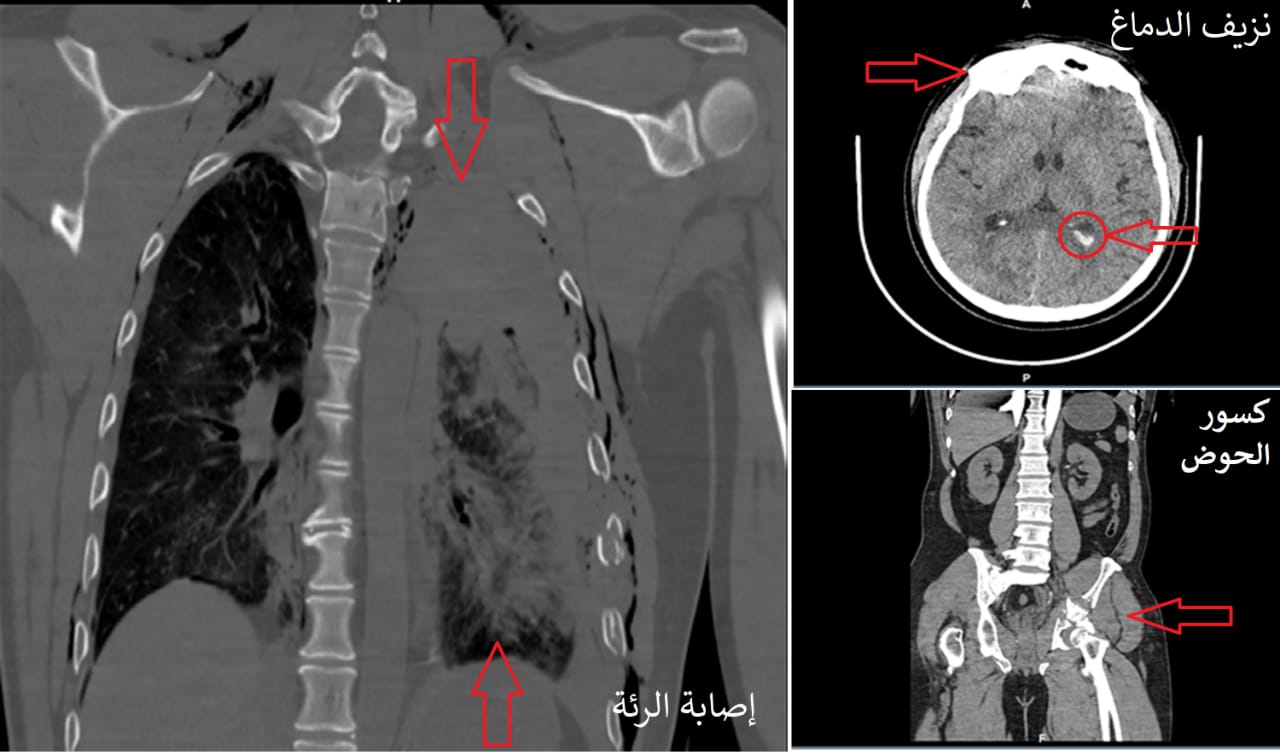

موضحاً بأنه بعد استقرار ضغط الدم لدى المريض تم إخضاعه للفحوصات الشعاعية بالأشعة العادية والتصوير المقطعي (C.T Scan) على منطقة الرأس والحوض والعمود الفقري، مشيراً إلى أن النتائج أبانت وجود نزيف داخل الجمجمة وآخر في الرئة ومنطقة الحوض، بالإضافة إلى حصر عدد 6 كسور في الضلوع الصدرية من جهة اليسار ، وكذلك اتضح دخول هواء للمنطقة الواقعة بين جدار الصدر والرئة أو ما يعرف بالاسترواح الصدري الأمر الذي يؤدي للضغط على الرئة.